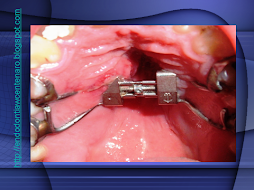

ENDO-OCLUSÃO

A ENDODONTIA PODE FRACASSAR SE A OCLUSÃO TIVER AJUSTADA

PELO DESGASTE APRESENTADO DA PARA IMAGINAR O QUE VAI ACONTECER!!!

SERÁ?

DOR!!!!!!!!!!!!!!!!!

É DA ENDO?

TINHA QUE DAR NISTO!!!!

E AGORA?